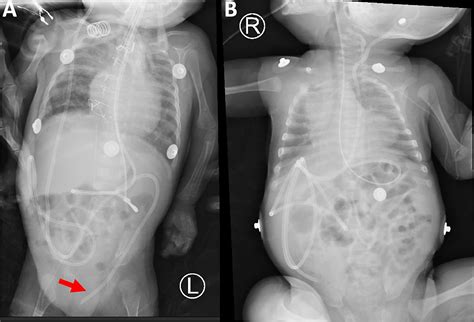

VP Shunt Placement Diagram